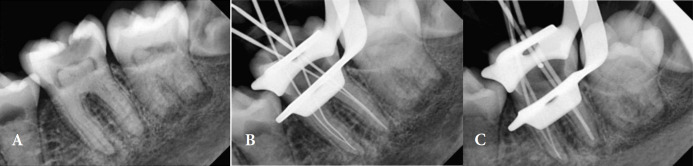

Dentin Dysplasia Type II (DD-II) is a rare genetic disorder that affects the coronal dentin, often leading to pulp stones and complicated endodontic treatment. This case report presents the endodontic management of DD-II in an 11-year-old female patient. The patient, referred for root canal treatment, exhibited symptoms of moderate pain and was diagnosed with pulp necrosis in tooth #19; radiographic findings revealed multiple pulp stones, pulp canal calcification, and apical radiolucency. Endodontic treatment was performed, involving the removal of pulp stones with ultrasonic tips, careful cleaning and shaping of the root canals, and obturation using gutta-percha and AH-26 sealer. Twelve months post-treatment, the patient showed complete healing of the apical lesion, with no related complications. This case underscores the importance of early diagnosis and timely endodontic intervention for favorable outcomes in patients with DD-II.